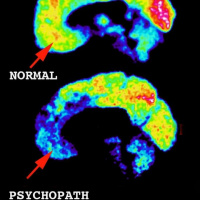

Ep. 23 Jim Fallon and the Psychopaths, Part 1

09/08/2016 Duration: 13minA neuroscientist makes an unsettling discovery.